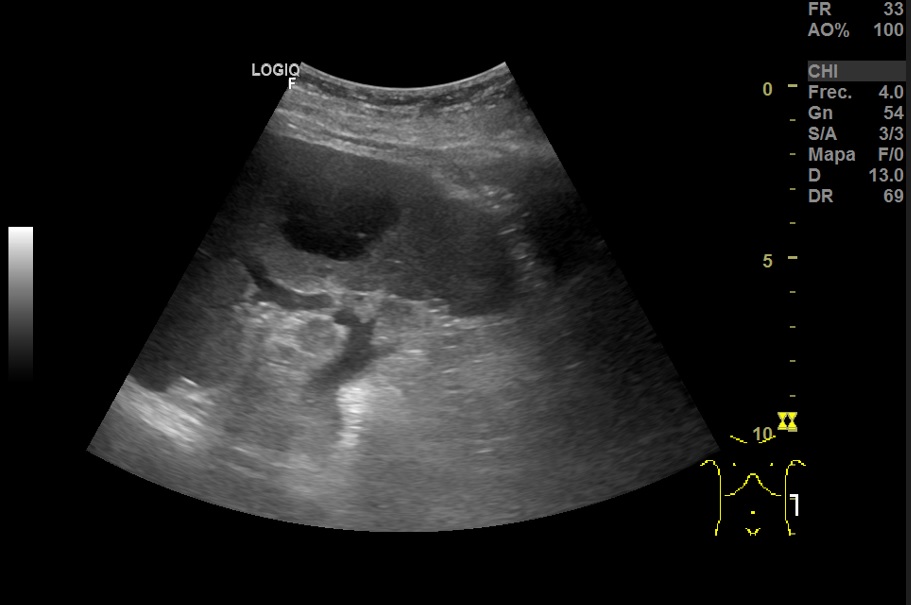

Hallazgos ecográfico: Esplenomegalia y varias lesiones focales hipoecogénicos de diferentes tamaños de bordes bien definidos en el bazo.

TAC abdominal: Bazo con múltiples imágenes hipodensas focales, mal delimitadas. Múltiples adenomegalias retrocrurales, mesentéricas, esplénicas y retroperitoneales.